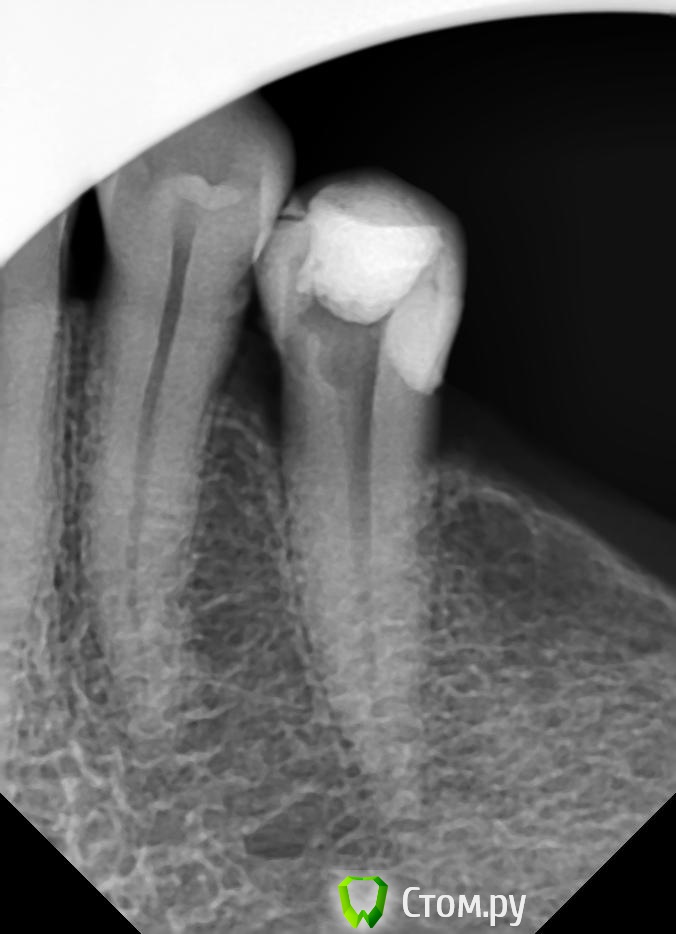

Л-Ф Опубликовано 23 апреля, 2014 Автор Поделиться Опубликовано 23 апреля, 2014 (изменено) Синяк у Вас, это гематома после укола, такое бывает... пройдет. Корневой канал еще не запдомбирован, поэтому сказать, что то о качестве не могу. Един ственный момент который сильно смущает это отсутствие снимков в процессе работыЗдравствуйте! Одним словом я обращалась далее в Стоматологическую больничку,в смотровой кабинет.По поводу ноющей боли.Мне убрали временную пломбу,почистили и закрыли опять временной пломбой.Боль сразу прошла и все было замечательно.Вот теперь 21 числа сходила и поставили постоянную пломбу.Вроде сразу ничего не болело при надкусывании на зуб сутки.А теперь появилась второй день боль при надкусывании острая и так ноющая немного,голова болит.Посмотрите пожалуйста снимок и дайте совет.Как мне быть.Однозначно у врача кривые руки.Что-то у нее не получается по хорошему.Почему,когда она мне запихивала пломбу в каналы у меня была боль,ведь мне убрали нервы.Почему сейчас вновь появилась боль ,по ощущению в корне зуба?Один снимок с временой пломбировкой,другой еще не совсем закрыт,только канал.Потом закрылиНомер зуба 35 Изменено 23 апреля, 2014 пользователем Л-Ф Ссылка на комментарий

sydnik Опубликовано 23 апреля, 2014 Поделиться Опубликовано 23 апреля, 2014 Здравствуйте!не ругайте врача(наверное долго лечила, вас это и насторожило ,ведь раньше пару минут и все готово ) ,по снимку все красиво,боль пройдет через пару дней 1 Ссылка на комментарий

Гарриевич Опубликовано 23 апреля, 2014 Поделиться Опубликовано 23 апреля, 2014 Снимок нормальный Болевые рецепторы у нас есть не только в нерве зуба, они есть еще и вокруг корня и где их только нет поэтому чувствовали боль когда материал выходил за верхушку корня, это ничего страшного, все пройдет Ссылка на комментарий

red_butler Опубликовано 23 апреля, 2014 Поделиться Опубликовано 23 апреля, 2014 Все хорошо, боль пройдет. Обязательно сделайте коронку. Судя по Вашему настрою, смена врача устроит и Вас и вашего стоматолога Ссылка на комментарий